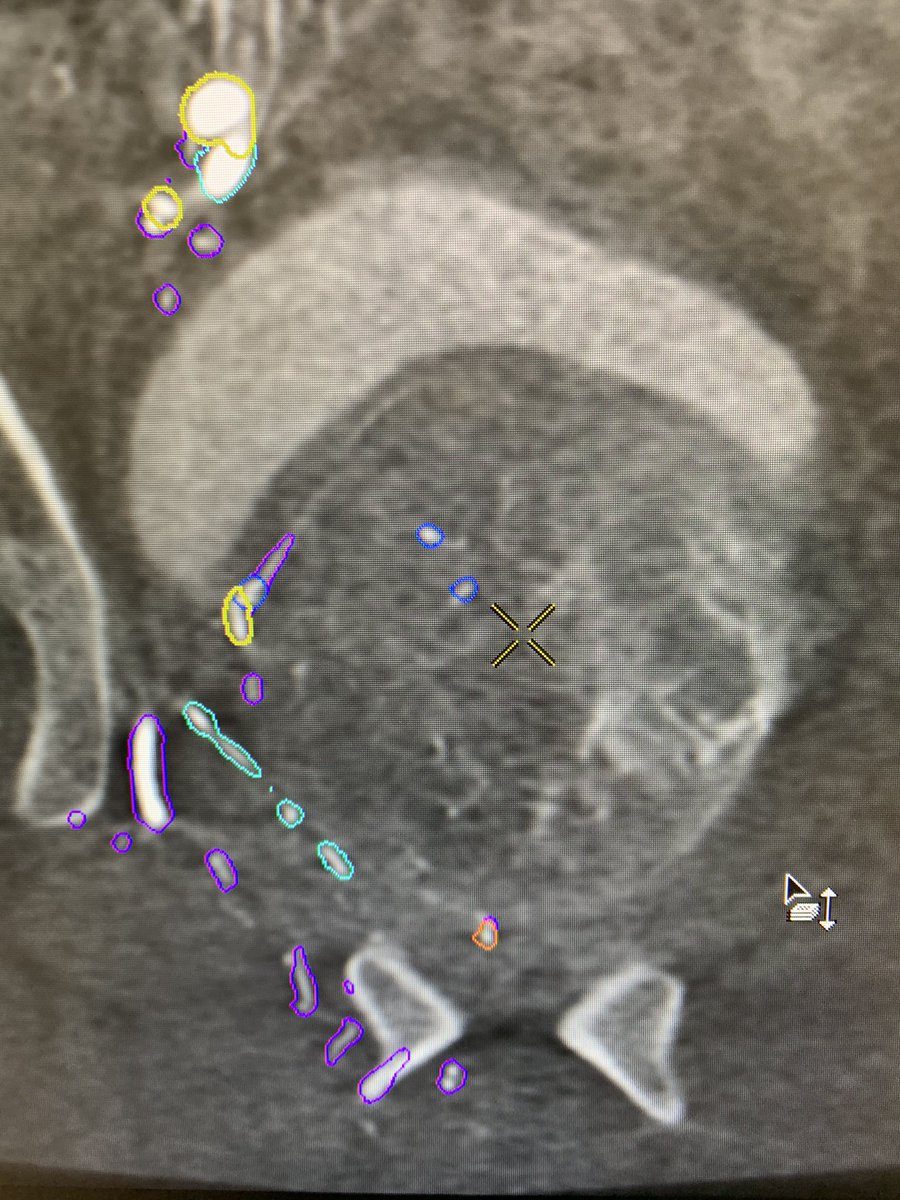

Nice example of multiple feeders to large prostate: yellow-main prostatic artery, orange-distal int pudendal (pena cava), teal-retropublic branch of obturator, pink-distal sup vesical. (Colors courtesy of GE) @SIRRFS @SIR_ECS @StreamMeeting @UsaProstate